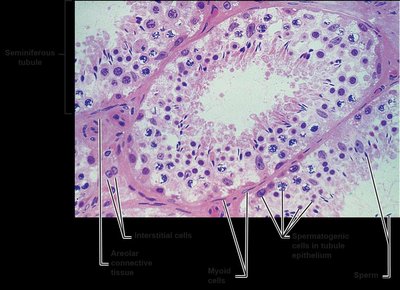

Each testis is surrounded by two tunics: the outer tunica vaginalis and the inner tunica albuginea. Septa divide the testis into lobules, each containing seminiferous tubules where spermatogenesis occurs. Interstitial (Leydig) cells between tubules produce androgens.

Section through testis showing seminiferous tubules, epididymis, and associated structures Histological section of seminiferous tubule showing spermatogenic and interstitial cells